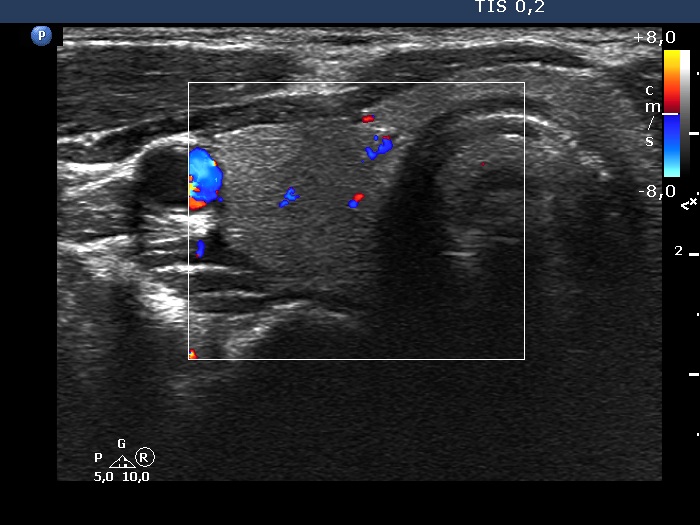

Ultrasonography. The thyroid was echonormal. On transverse scan, a minimally-moderately hypoechoic areas was found in the ventral part of the right lobe. Just ventral to this area, there was a thick connective tissue band within the strap muscle. This area could not be detected on longitudinal scan.

Comment. Anatomical structures ventral to the thyroid influence the penetration of ultrasound wave. The two most common examples are the acoustic shadowing caused by macrocalcifications and the opposite, the acoustic amplification dorsal to cystic fluid. In this case, the thickened connective tissue impaired the penetrance of ultrasound wave and decreased the echogenicity of the thyroid dorsal to this thickening.